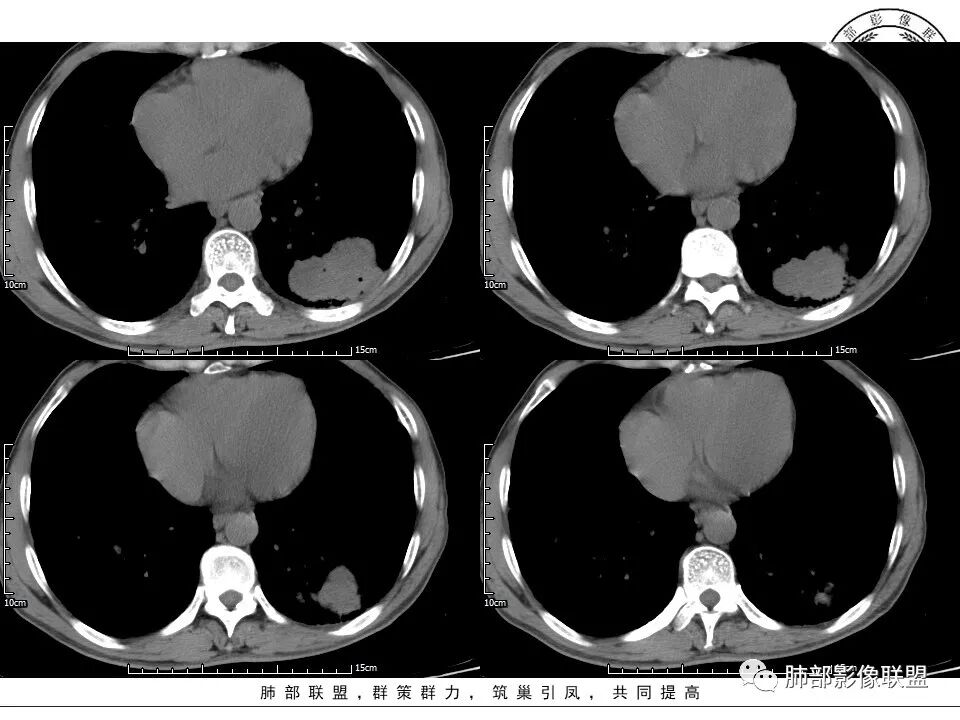

1、老年男性,肺气肿背景,咳嗽胸闷一个月,血象不高,C反应蛋白无明显升高,无发热。

2、左肺下叶近胸膜下较大肿块,土豆样外形,边缘清楚,膨隆分叶,未见明显渗出;病灶内部多坏死及空洞,似鬼脸征,坏死边界不清;增强扫描轻度不均匀环形强化;近端支气管似有阻塞截断。肺门纵隔未见肿大淋巴结。

3、综上所述,考虑恶性,鳞癌可能。

老年男性,咳嗽、胸闷1月余。胸部CT:左肺下叶胸膜下不规则肿块,边缘光滑,边界清楚,见浅分叶,其内见多发分隔空洞及坏死,增强不均匀强化。考虑恶性病变,鳞癌,鉴别隐球菌。

患者中老年男性,咳嗽、胸闷1月余。查肝肾功能、血糖、血脂、心肌酶异常不明显;血常规提示血象不高,轻度贫血;血沉、C反应蛋白、降钙素原无明显升高。胸部CT:肺气肿背景,左肺下叶胸膜下不规则肿块,边缘光滑,边界清楚,见浅分叶,其内见多发分隔空洞及坏死,似鬼脸征,支气管显示欠清,增强不均匀强化。右肺下叶胸膜下间质纤维化改变。综合肿块考虑恶性病变,鳞癌或肉瘤样癌可能大,鉴别隐球菌。